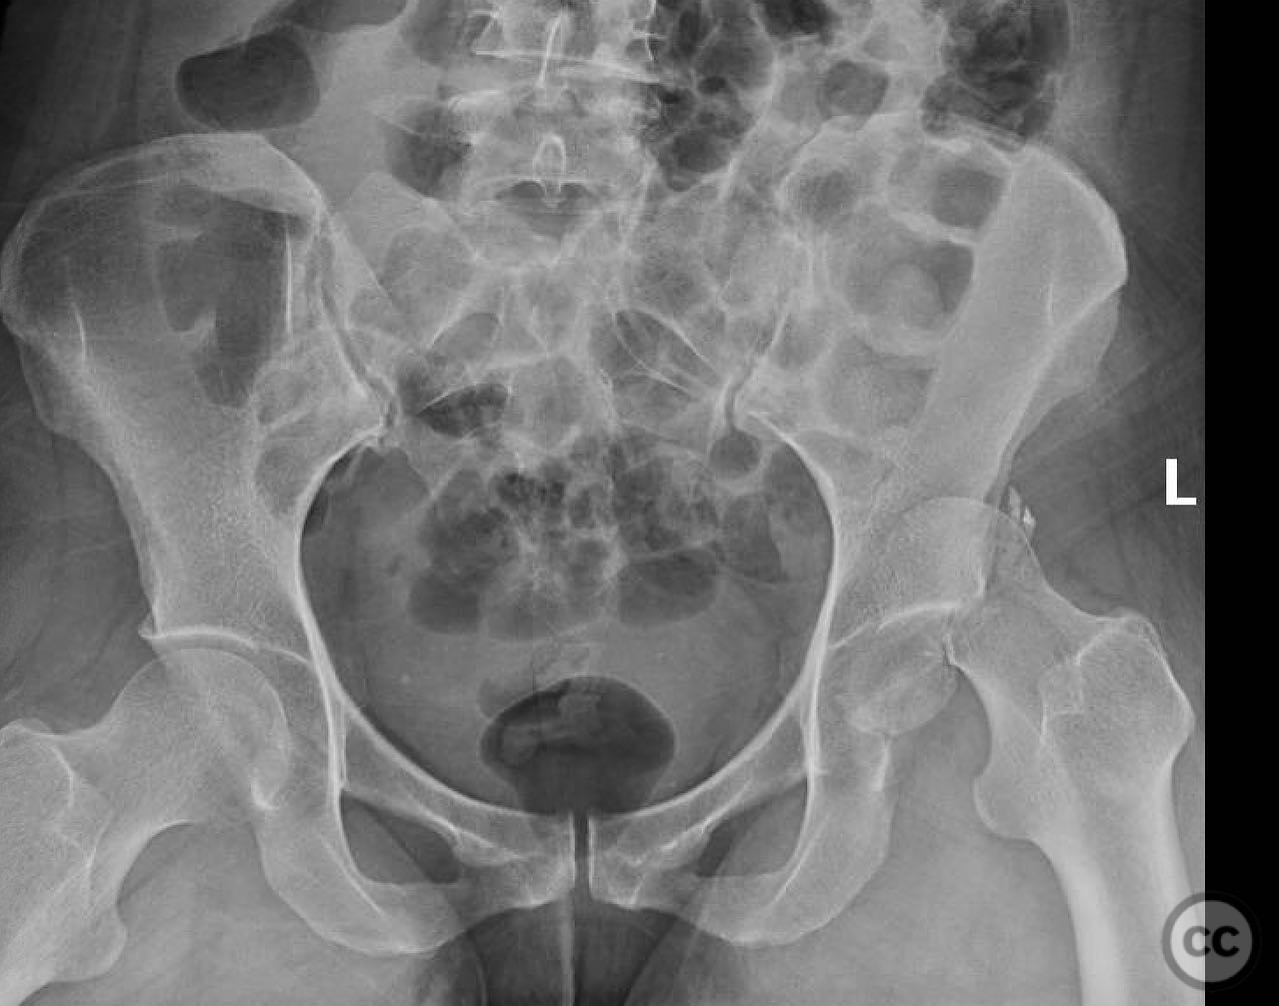

Pipkin IV Femoral Head Fracture with Ace...

Seattle, United States

Femur - AO/OTA 3x

Pipkin IV Femoral Head Fracture Dislocat...

Pipkin IV Femoral Head Fracture with Fem...

Pipkin Type III Femoral Head and Neck Fr...

Pipkin 2 + cranial peripheral acetabular...